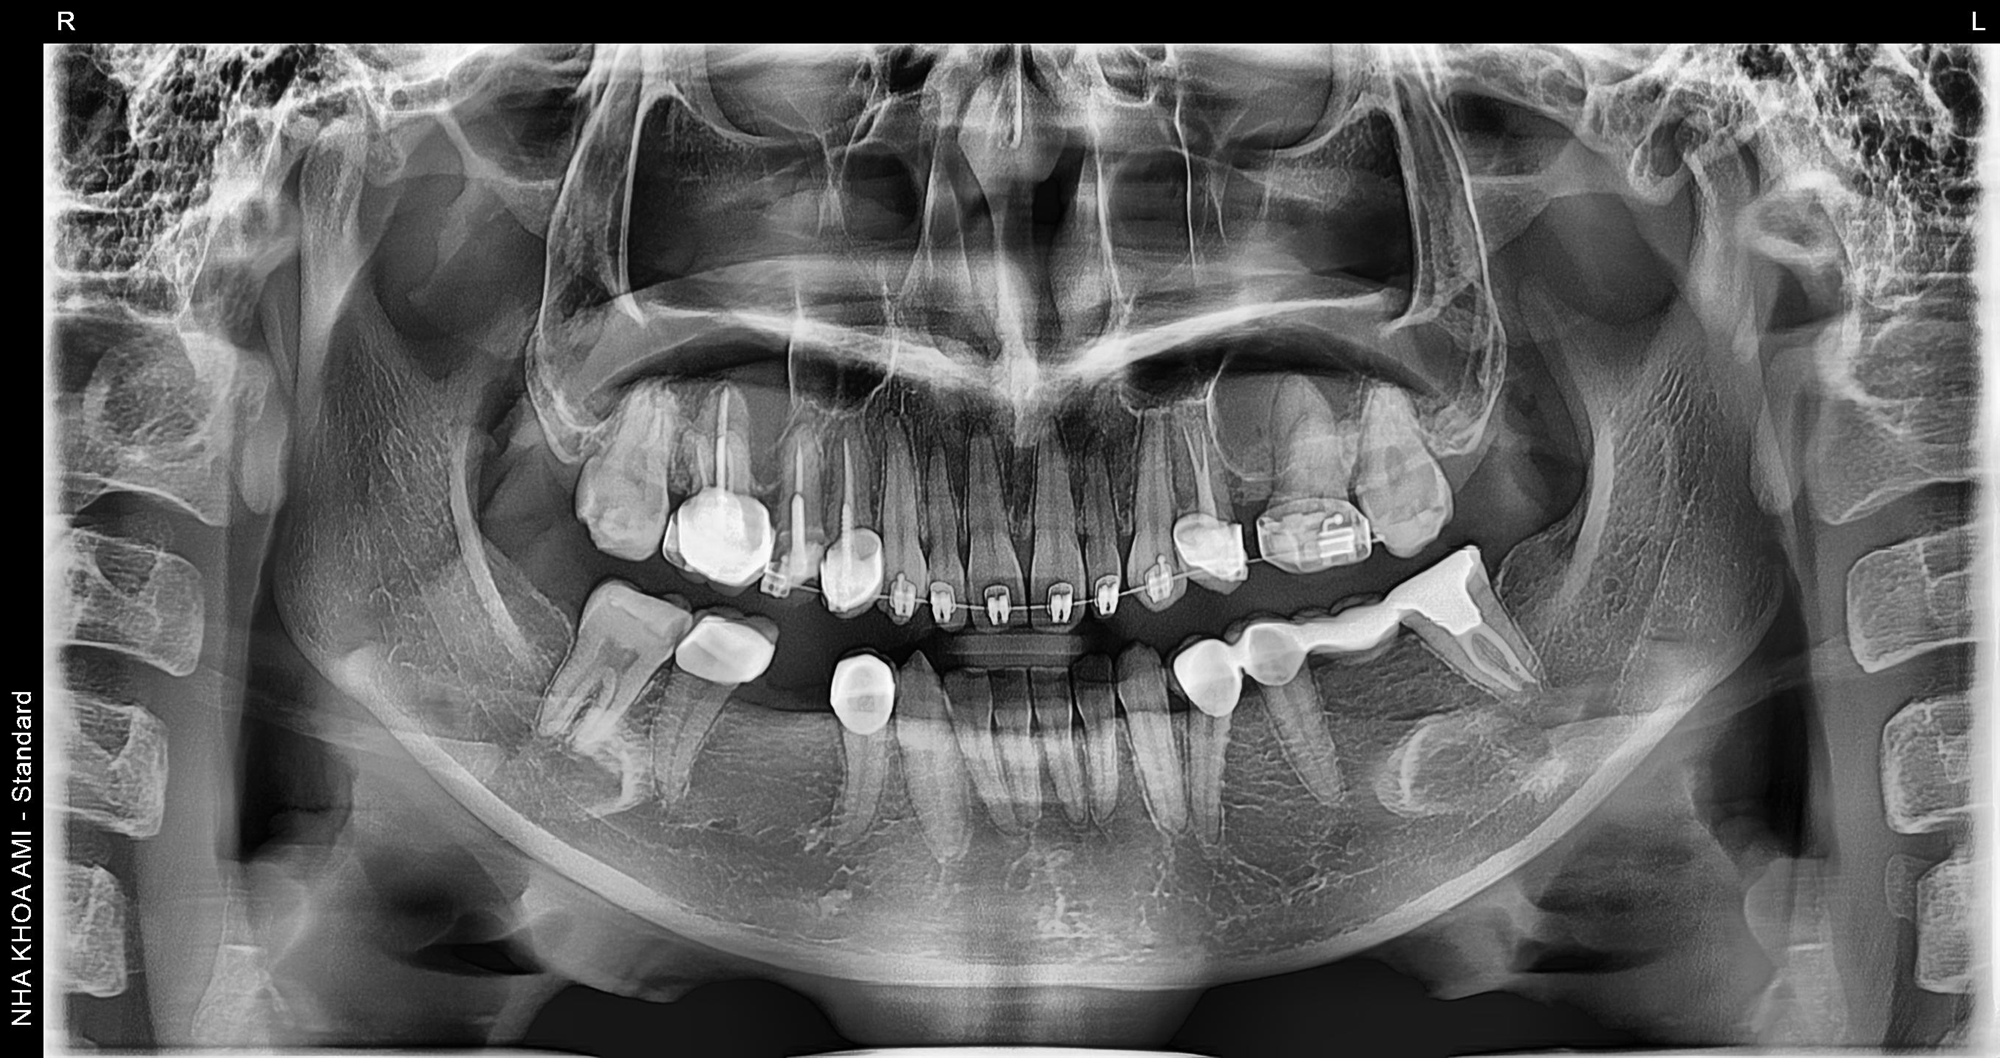

Hình ảnh X-quang cận cảnh giúp bác sĩ tại AMi kiểm soát cấu trúc xương và chân răng, đảm bảo quá trình niềng răng diễn ra an toàn ngay cả trên nền răng đã làm sứ.